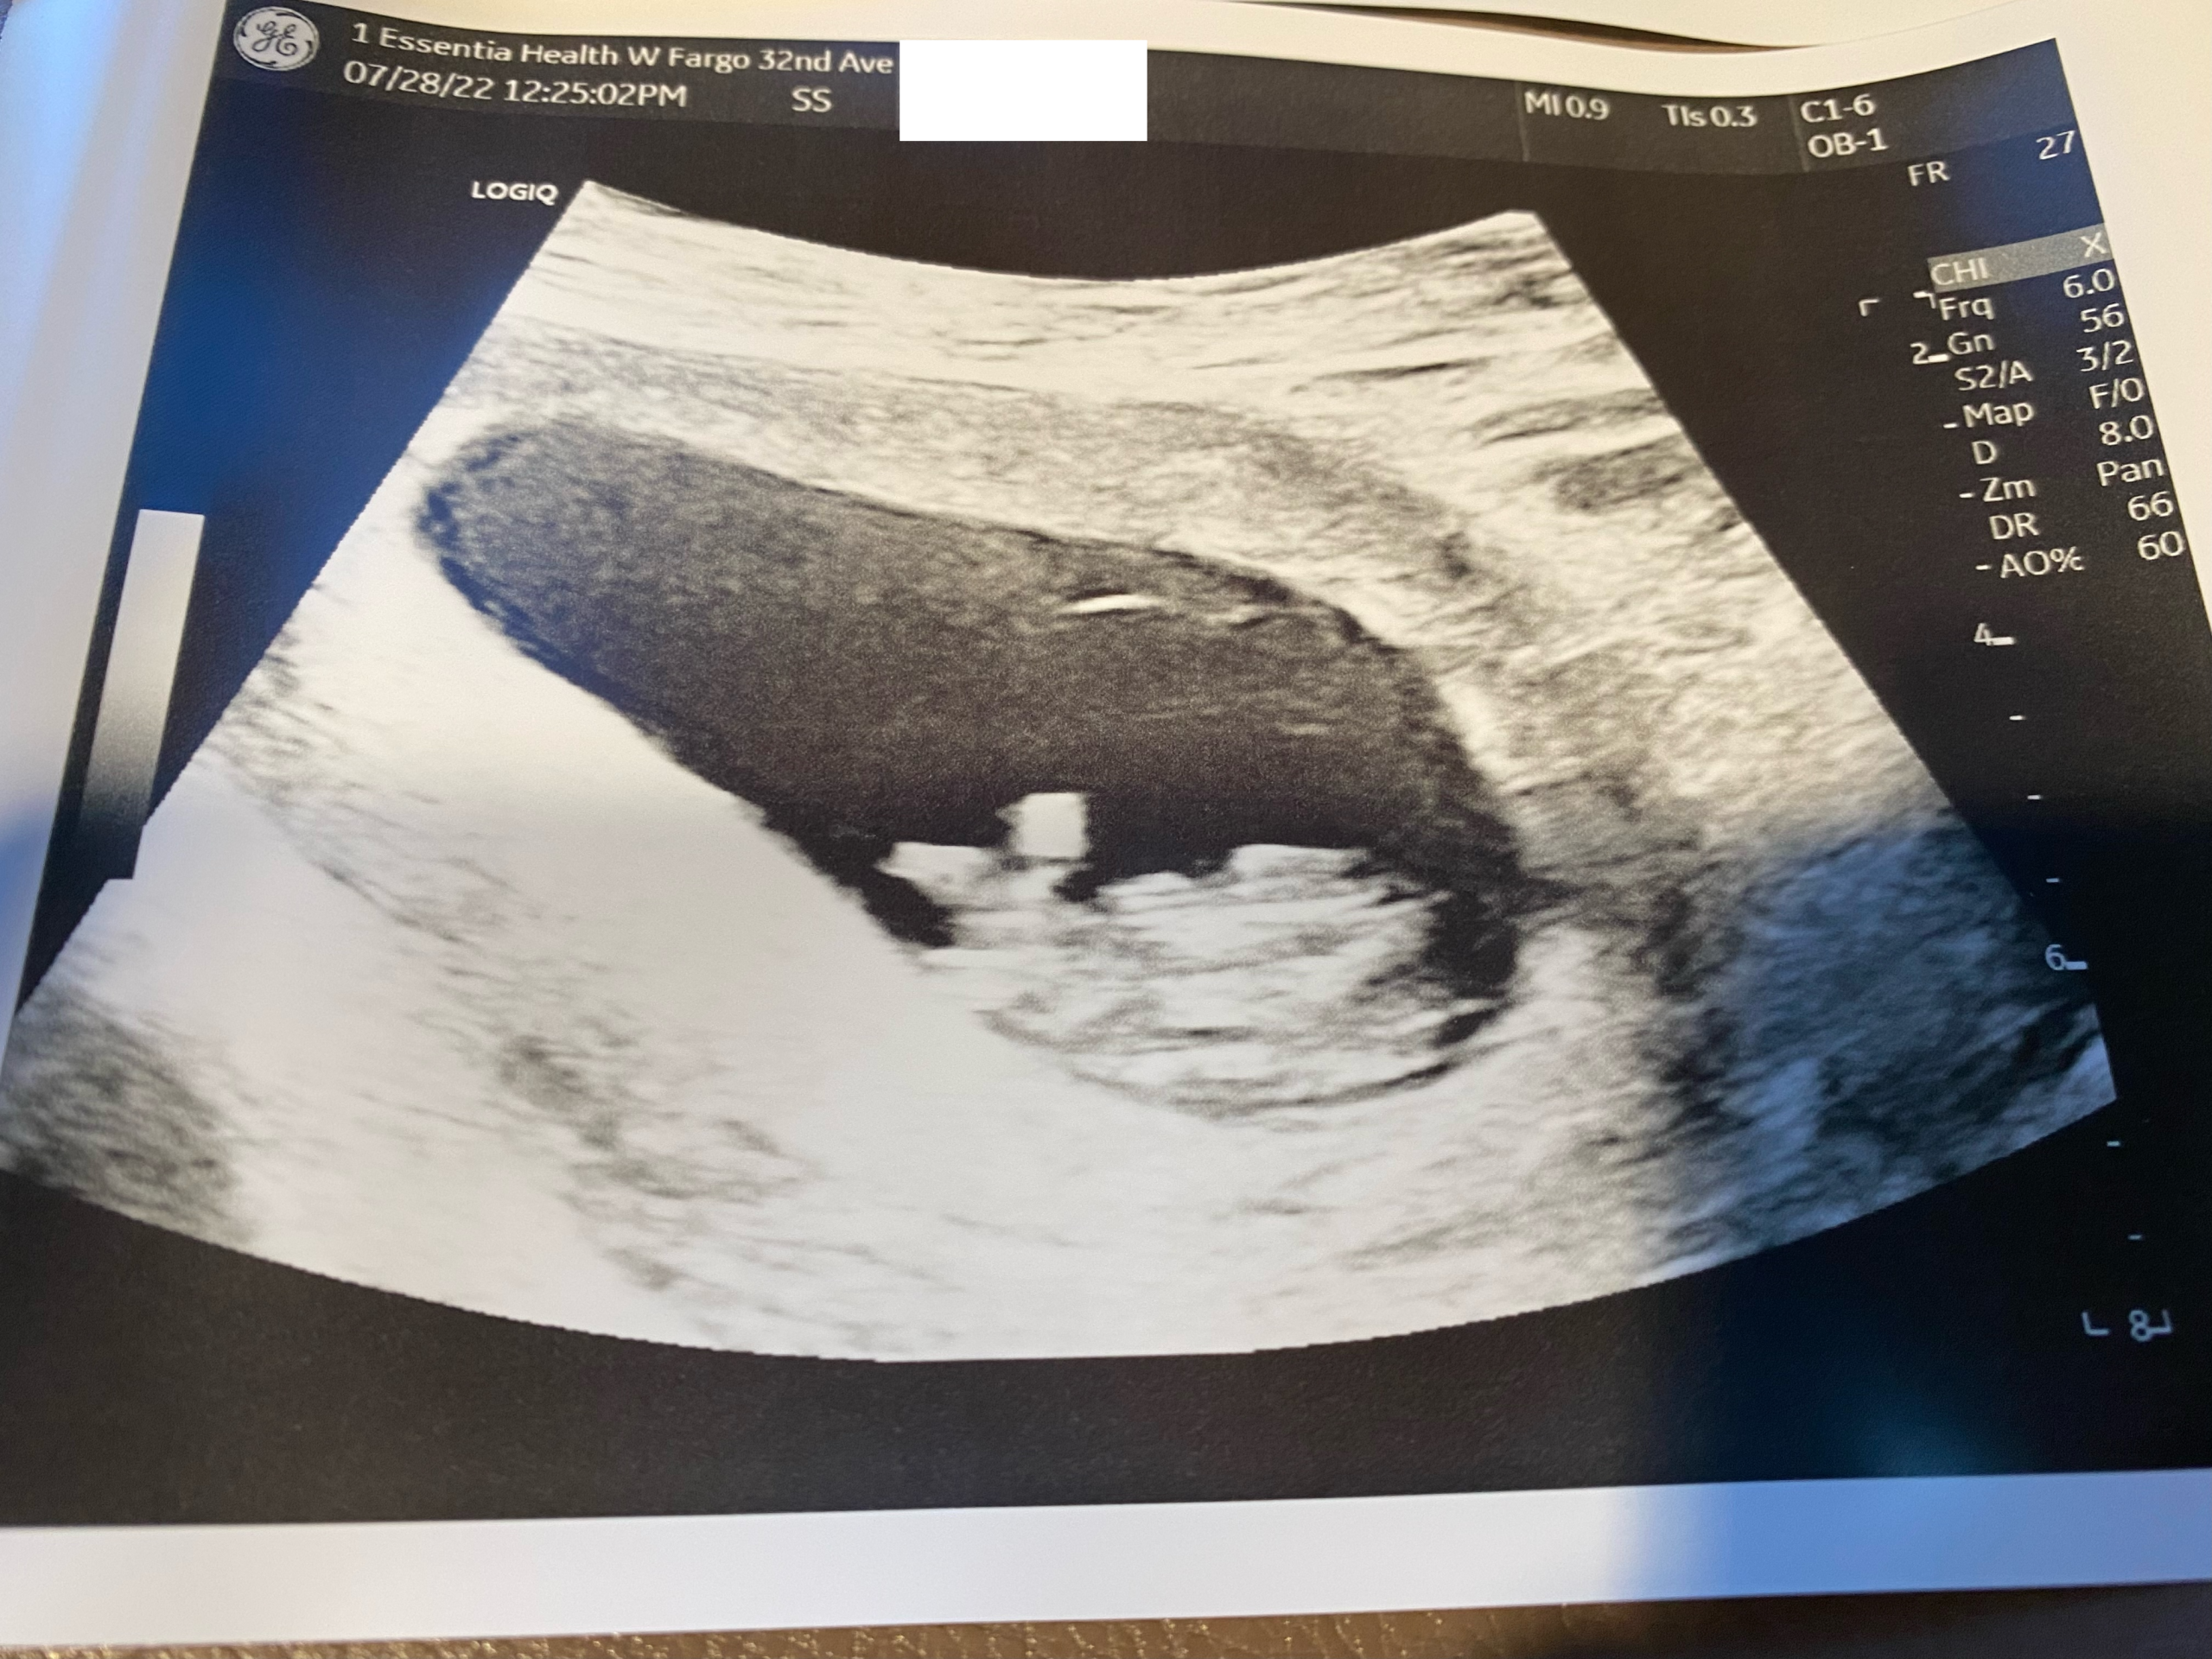

August Update (2022) ☀️

We just wanted to get a quick update out to keep everyone posted, but everything has been going very well still! On July 28th we met up with Jane in Fargo and had our second

Read More »

August 8, 2022